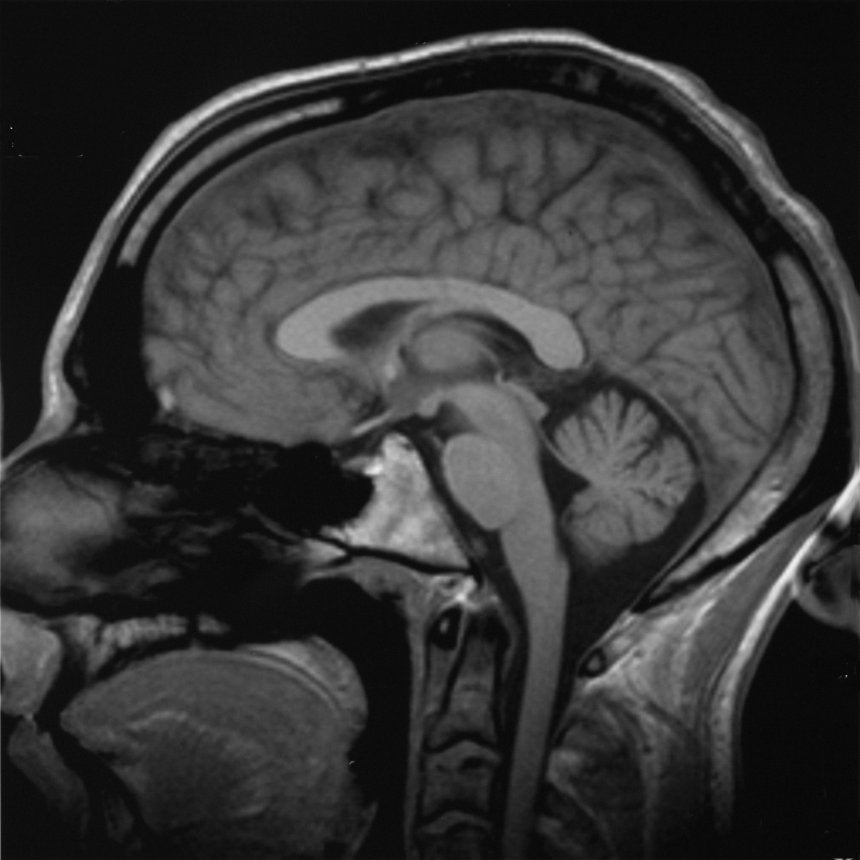

Are Lab-Grown “Minibrains” Ethical?

Today, scientists can create bits of human brain to mimic and study the human condition. But without a clear understanding of human consciousness, some are worried about how ethical the research is. A bioethicist joins us to discuss life’s big questions.